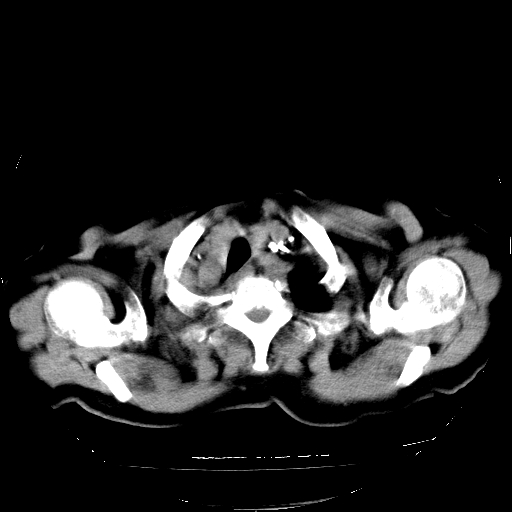

标题: CT23991:女,72岁,咳嗽、憋气一周。 [打印本页]

女,72岁,咳嗽、憋气一周,十年前曾患肺结核及胸膜结核。

1.右侧损毁肺伴胸膜钙化,2.左肺小结节灶,良性可能大,注意复查。3.肝脏左叶囊肿。4.先天性一侧肺不发育待出外(右侧胸廓无明显塌陷)。对比原片应该非常有帮助。

支持楼上,肝脏多发囊肿